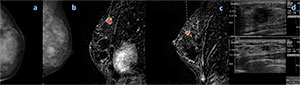

Figure 1. Mammography and MR imaging in a 46-year-old woman with a palpable mass in the right breast. A: Mediolateral oblique (left) and spot compression (right) mammograms in the right breast show a mass in the upper-outer quadrant. B: Sagittal dynamic breast MR images in the right breast show an en-hancing mass with speculated, or spiky, margins in the right upper outer quadrant, an additional focus near the nipple (DCIS), and nonmass enhancement in the inferior quadrants (DCIS). The additional lesions were not visible at US and were biopsied with MR imaging guidance.